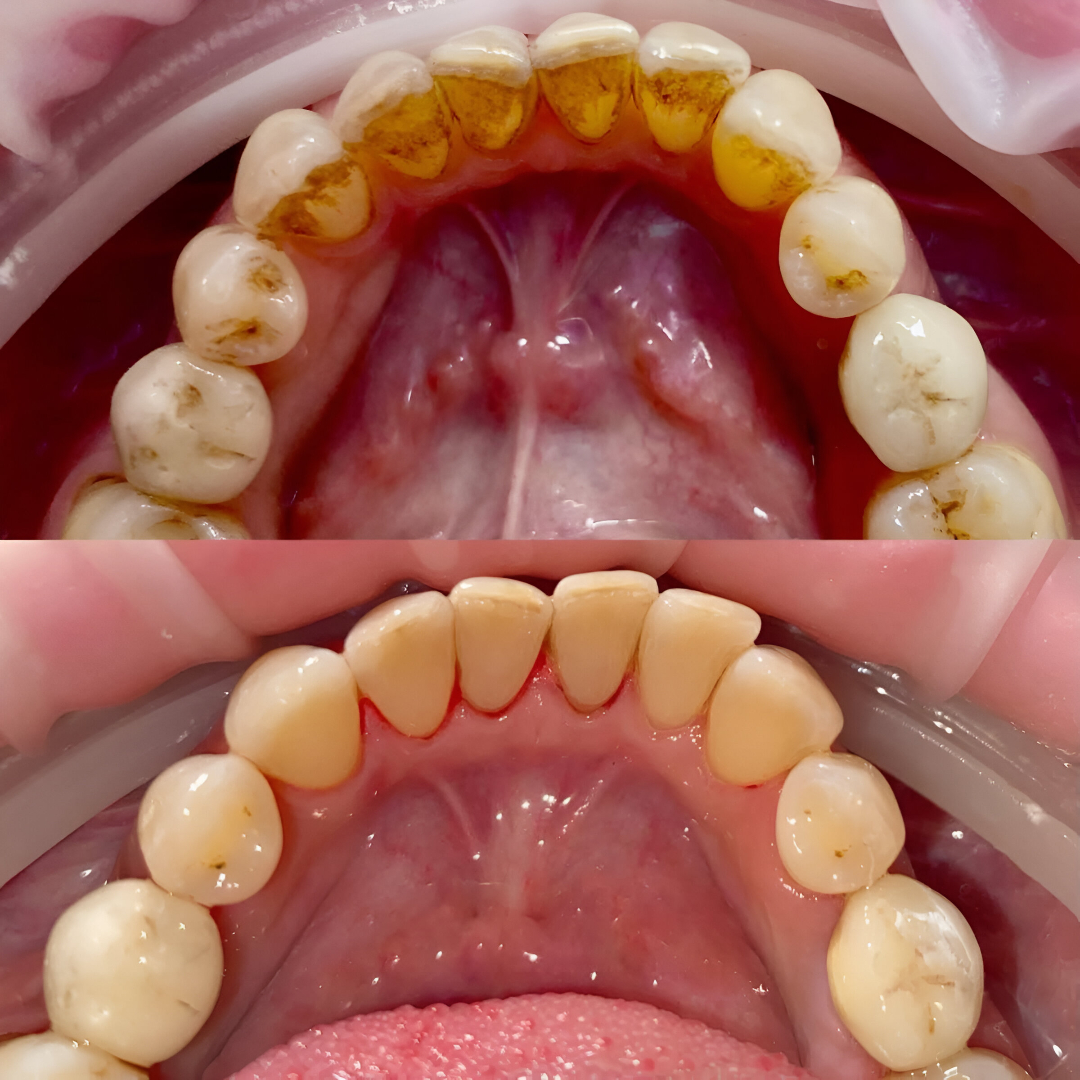

General Dentistry (Cleanings, Exams)

Ultrasonic cleaners, digital x-rays

Periodontal Treatment

Laser therapy, ultrasonic scalers